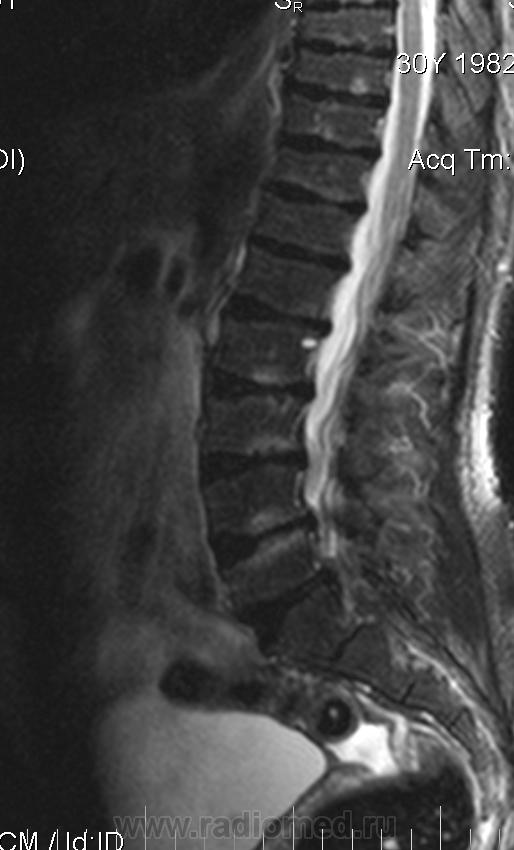

Мужчина 30 лет, рост 151см

Уважаемые колллеги, помогите, пожалуйста. Изменение формы тел позвонков. Остеохондропатия?

Изменения позвонков типичны для спондилоэпифизарной дисплазии.

Для спондилоэпифизарной дисплазии типична деформация позвонков по типу "переднего языка", платиспондилия, низкорослость, при Шойерман-Мау деформация позвонков другого типа.

Нет, это снижение высоты в переднем отделе тела позвонка за счет недоразвития апофизов. Чем отличается платиспондилия от брахиспондилии не знаю, тоже всегда хотелось узнать, но нигде четкого разграничения не находила. Где то читала, что при платиспондилии отмечается снижение высоты тел при одновременном их расширении. Ссылок нет.